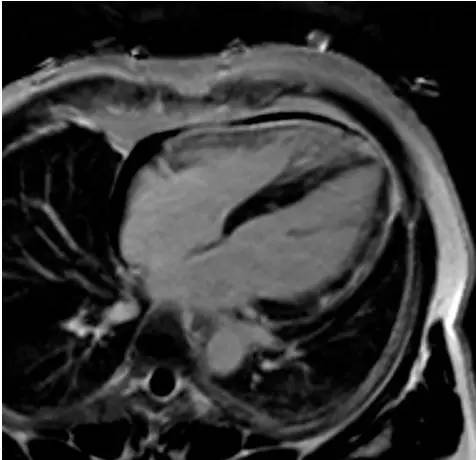

2. 患者行心脏磁共振检查,图像如下,可见哪些阳性表现(多选):

答案:ABCEH

解析:电影序列舒张末期四腔心图像示心室形态未见明显异常。T2黑血序列短轴、四腔心图像示左室侧壁、室间隔多发片状T2高信号。短轴、四腔心图像示心肌静息首过灌注未见明显异常。延迟扫描短轴、四腔心图像示左室侧壁、室间隔心外膜下及心肌内多发条片状及斑片状延迟强化。